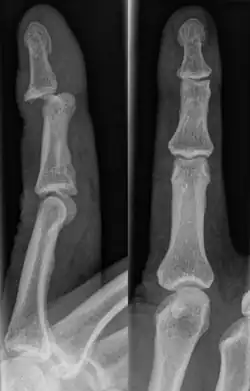

The injured finger may be examined to determine where the pain is worst.[3] If the finger is sprained or dislocated, pain will be worse at the joint rather than the bone.[3] Due to the risk of dislocations or fractures, X-rays should be conducted prior to testing joint stability. This allows for prior detection of a dislocation or fracture.[3] It is recommended that a variety of views (lateral, oblique, and anteroposterior) are observed.[3] In extremely painful cases, a digital nerve block may be done to better assess the finger. This is where anesthetic is injected to either side of the base of the affected finger to reduce pain.[3]

Injuries that force the finger towards the back of the hand may cause damage to the volar plate.[12] This is a ligament on the palm side of the hand that prevents hyperextension.[13] Volar plate damage may be assessed by pressing the finger bones from the back towards the palm. If either individual bone of the affected joint moves freely towards the palm, it is indicative of a tear.[2] Tears of the volar plate may lead to an avulsion fracture – when a piece of bone is pulled off with the ligament.[13] This is due to the thickness and strength of the ligament.[14] To rule out an avulsion fracture, x-rays are frequently utilized in evaluation of suspected volar plate tears.[12] Volar plate avulsions are most evident on lateral views.[2]

Dislocations are often visually obvious due to joint deformity.[2] Therefore, x-rays may or may not be utilized in the diagnosis of a suspected dislocation. Though, they can provide feedback on post-reduction status if attempted prior to formal medical evaluation.[2] Dislocations may also be complicated by a tandem fracture.[5] These cases may necessitate a visit to a hand surgeon for surgery.[2]

Fractures

Fractures are instances where the bone's structural integrity has been compromised.[20] If a jammed finger produces a fracture, pain will be greatest at the bone as opposed to the joint.[2] There may also be visual deformation of the bone itself.[6] As with any skeletal injury, an x-ray can be conducted to verify the presence of a fracture.[1] The distal phalanx is especially vulnerable to avulsion fractures.[1] These avulsion fractures are common following a first time dislocation of the DIP.[1]